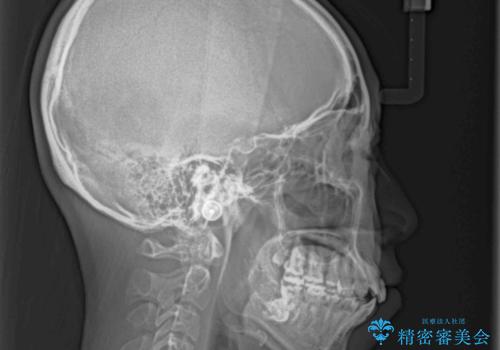

- 口元の突出感を気にして来院された患者様です。

診断の結果、上顎左右第一小臼歯4本抜歯により、叢生を解消するとともに口元を引っ込めていくことが望ましいと判断しました。

抜歯矯正による口元の改善にはワイヤー矯正が望ましいのですが、ダンサーとしての仕事を行っているため、インビザラインにて治療を行うこととしました。